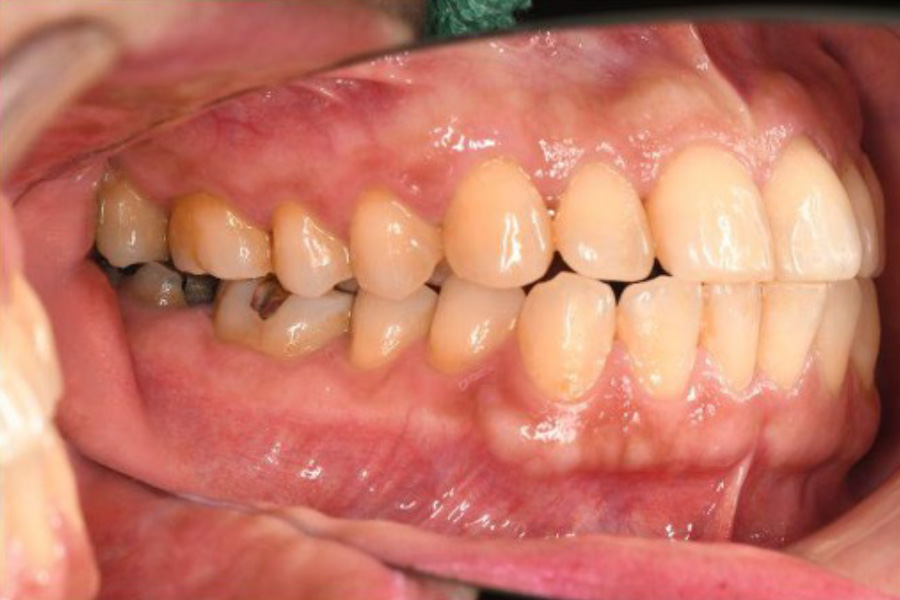

治療前

| 主訴 | 左奥歯が仕事が忙しくなると上下とも痛くなる。 毎月メインテナンスしていた歯科医院が閉院した。 歯周病含め今の状態が気になる。 全体のメインテナンスもしたい。矯正治療はやりたくない。 |

| 治療内容 | 全顎治療:歯周病治療、根管治療、 歯肉弁剥離掻爬術(フラップ手術)、 セラミック治療、ダイレクトボンディング |